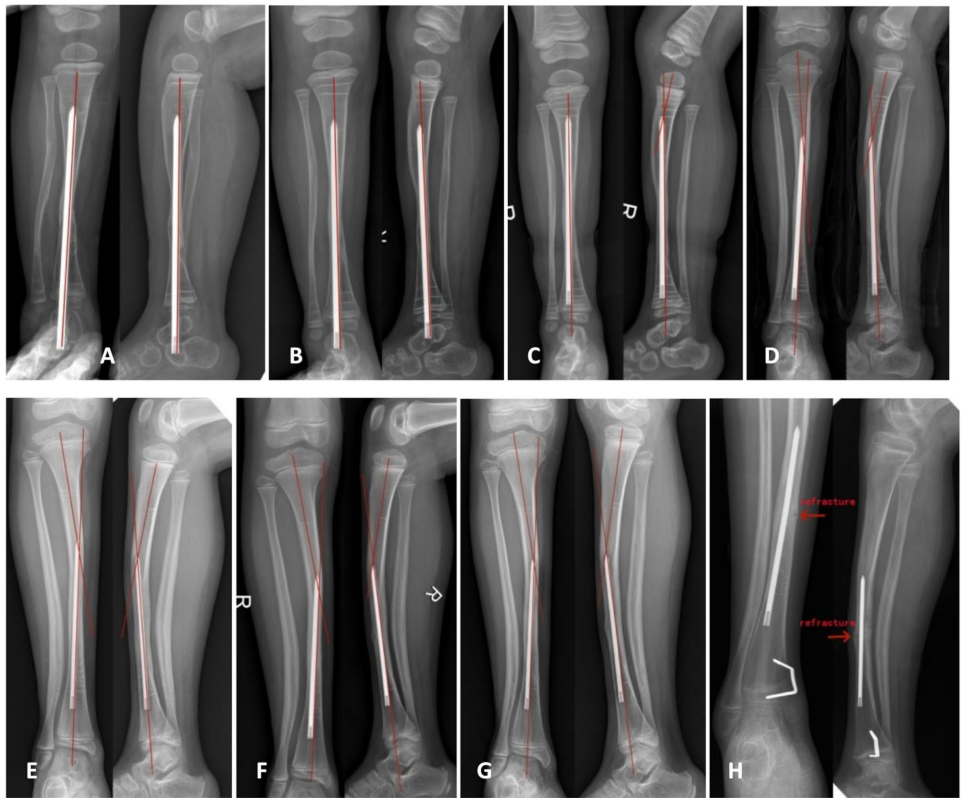

湖南省儿童医院骨科团队在《Orphanet Journal of Rare Diseases》发表的研究,通过82例Crawford IV型CPT患儿长达7-12年的随访,系统评估了跨踝关节髓内钉固定联合手术的长期疗效。这项目前最大样本量的单中心研究揭示:虽然联合手术能实现100%的初始骨愈合,但髓内钉的后期处理方式直接影响并发症发生率——当髓内钉完全插入胫骨髓腔保留时,100%出现髓内钉偏移,70.3%并发胫骨发育性弯曲畸形,40.5%发生再骨折;而维持跨踝固定组仅8%再骨折率,且无畸形发生。

研究采用四步联合术式:1) 彻底切除假关节及周围错构瘤样组织;2) Williams髓内钉经踝关节固定维持胫骨力线;3) 自体髂骨半圆柱形皮质骨包裹移植联合松质骨填塞;4) Ilizarov外固定架加压固定。术后通过RUST评分系统评估骨愈合,采用PACS系统测量胫骨力线参数。

82例患儿平均手术年龄43.17±13.40个月,初始骨愈合时间4.16±0.65个月,平均随访119.78±20.08个月,所有病例均实现初始愈合。